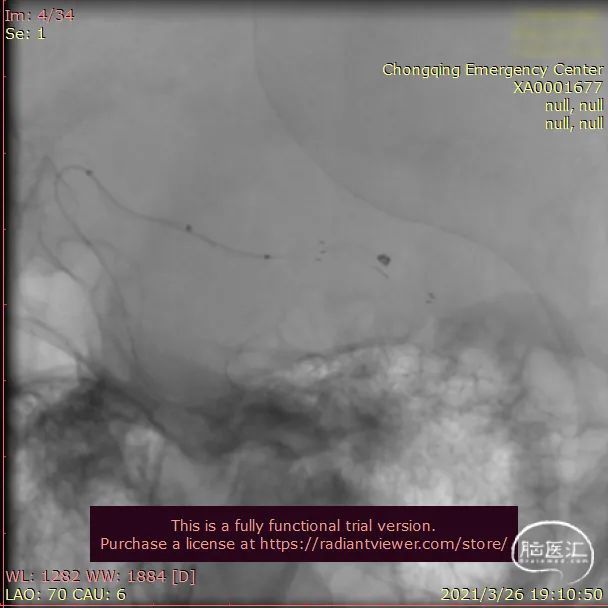

全麻后患者血压偏低,需升压药物维持,由于三系统操作更为复杂,遂决定进行双系统治疗。右侧颈内动脉近端置入6F导引导管, Synchro 0.014" 200cm微导丝引导SL-10微导管(支架导管)跨过动脉瘤放置到位,头端位于M2段;微导丝+ SL-10微导管塑形后,先跨过动脉瘤,然后回撤微导管,靠微导管的预塑形顺利进入瘤腔,防止微导管刺破动脉瘤。先使用Target 6mm*30cm尝试成篮。

动脉瘤为绝对宽颈,弹簧圈无法成篮,先半释放4.5mm*30mm Neuroform Atlas支架覆盖部分瘤颈,但弹簧圈仍突出于载瘤动脉,完全释放支架。头端位于颈内动脉末段,尾端位于眼段,支架顺利释放,Mark点显影良好。

放置Target 6mm*30cm和Target 4mm*15cm进行填塞,后期微导管位置不理想,弹簧圈反复被顶入载瘤动脉,通过支架网孔再次放置微导管。穿网孔后再相继填入Target 2mm*6cm、ES 2mm*6cm、ES 1.5mm*4cm

术后即刻影像

治疗后工作位减影造影显示动脉瘤致密栓塞,子囊未显影载瘤动脉血流通畅。